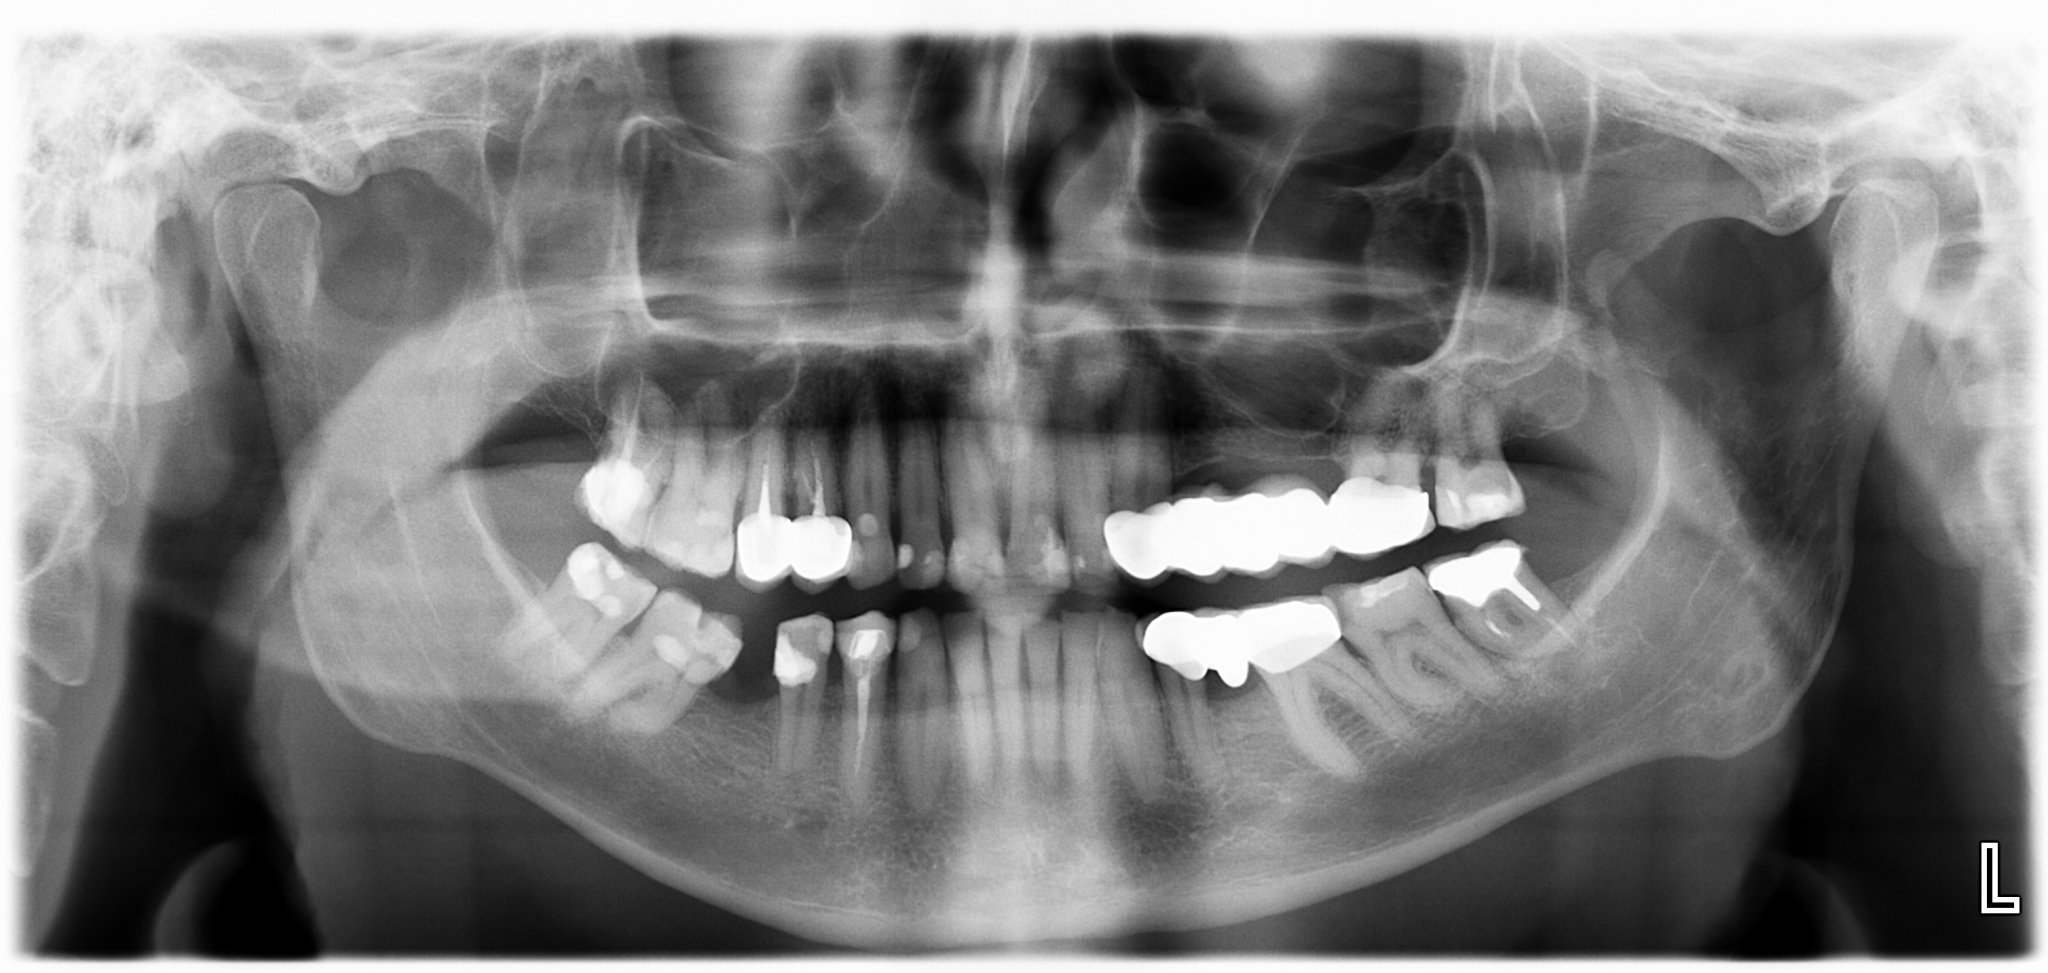

Има дори хора, на които каналите са били запълнени, години след това са направили гранулом, стоматологът е пробил запълнените канали и го е излекувал. При това на мъдрец! Без да се използва микроскоп или ендоскоп.

Грануломът е ограден в червено:

На следващата година положението е по-зле:

След 9 месеца лечение, повторно запълване на канала и поставяне на метало-керамична коронка с пинлей: